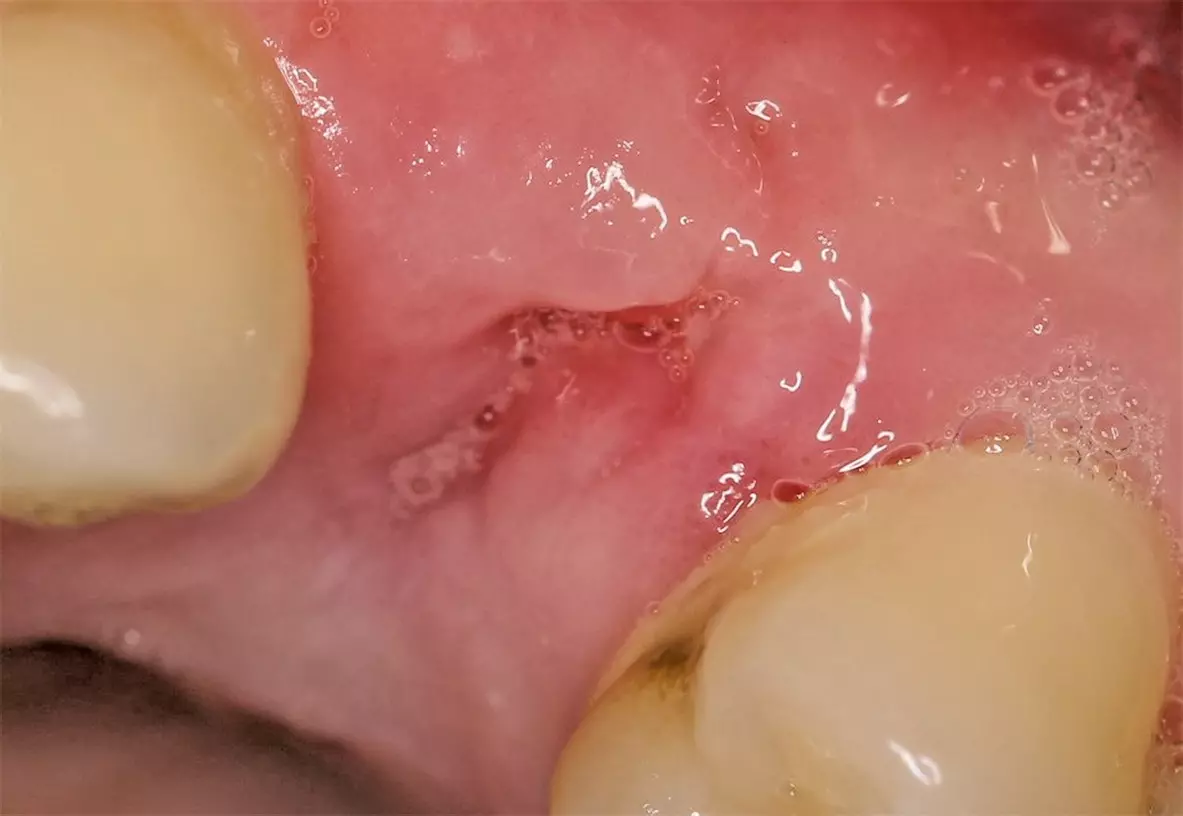

Nach ausführlicher Aufklärung und Beratung wurde die Extraktion des Zahnes 24 geplant. Zu diesem Zeitpunkt entschied sich der Patient gegen eine präventive Maßnahme zur Versorgung der Extraktionsalveole. Eine schonende Extraktion des Zahnes erfolgte komplikationslos unter gängiger Lokalanästhesie. Dabei konnte die vestibuläre Lamelle regelrecht erhalten werden (Abb. 2). Die Extraktionsalveole wurde mit einer Naht versorgt (Abb. 3). Ein Tag nach der Extraktion zeigt sich eine fibrinbelegte Wunde mit zeitgerechter und regelrechter Wundheilungsstatus (Abb. 4). Nach einer Woche wurde die Naht entfernt. Es zeigte sich zu diesem Zeitpunkt weiterhin eine fibrinbelegte Wunde mit einer okklusalen Mulde, die etwa 5 mm tief ist. Die Heilung war nach einer Woche also noch nicht komplett abgeschlossen (Abb. 5). In der frühen Wundheilungsphase berichtete der Patient beschwerdefrei gewesen zu sein. Drei Monate später stellte sich der Patient erneut vor mit dem Wunsch einen festsitzenden Zahnersatz zu bekommen. Die Extraktionsalveole zeigte eine vollständige Wundheilung und eine deutliche vestibuläre Knochenresorption (Abb. 6). Das Implantat konnte trotzdem eingesetzt werden und zeigt zum Zeitpunkt der Implantation eine adäquate Primärstabilität (Abb. 7). Nach drei Monaten wurde das Implantat freigelegt (Abb. 8) und anschließend mit einer Krone versorgt (Abb. 9).